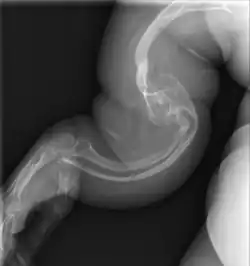

![]() несовершенный остеогенез V типа у взрослого | |